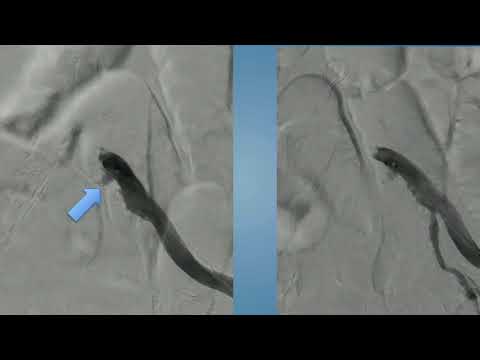

CVI2018 Session: Perforated iliac, how to bail myself out - Sahil Parikh, MD